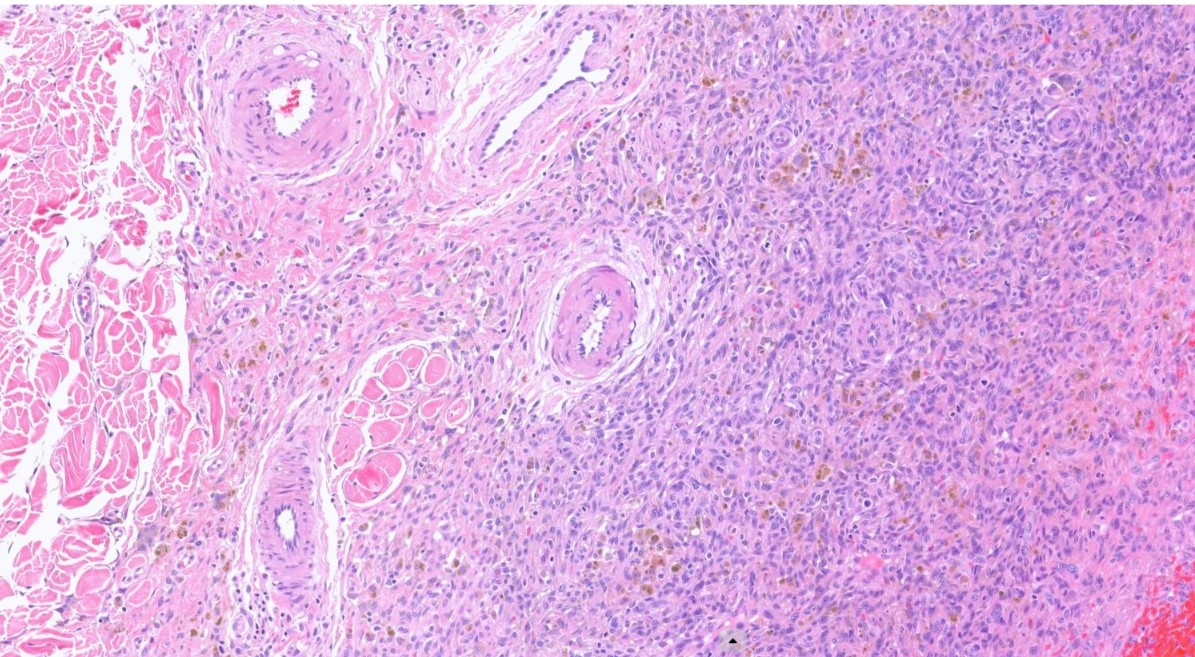

16M, Back-Excision ? Angioma